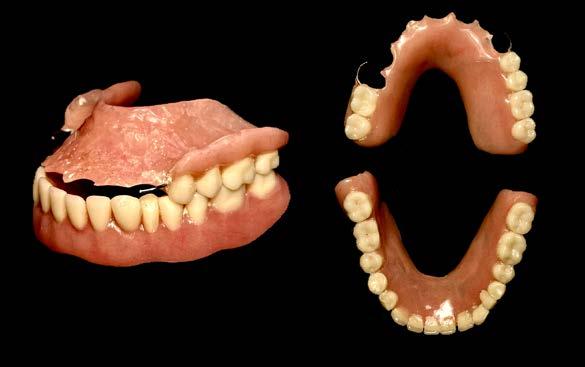

hace 8 años por lo que toma 30 mg de nifedipino cada 12 horas, amlodipino 5 mg cada 24 horas, telmisartan 40 mg cada 12 horas y metropolol 100 mg cada 12 horas, además comenta padecer diabetes mellitus tipo II desde hace 7 años por lo que también toma 50 mg de metformina cada 12 horas y dapagliflozina 10 mg cada 24 horas. Clínicamente se observó una encía roja y sangrante, profundos sondeos, una notable hiperplasia gingival, depósitos de cálculo y movilidad dental grado III en todos los órganos dentarios a excepción del segundo premolar superior derecho al canino superior izquierdo, quienes presentaban una movilidad grado II. Radiográficamente se encontró una pérdida de inserción radiográfica avanzada generalizada

en la arcada inferior, y grupos molares de ambos cuadrantes superiores (Figura 1), los únicos órganos dentarios con posibilidad de preservación en boca a través de terapia periodontal se encontraron en el sector anterior de la arcada superior anteriormente mencionados con movilidad grado II

(Figura 2). Por lo que se diagnostica con periodontitis generalizada, estado IV, grado C (Figura 3).

en función en boca (Figura 4) y planificar el tratamiento a través de un proceso protésico-quirúrgico, el cual consistiría en la elaboración de prótesis inmediatas, pues debido a la gran

destrucción de los tejidos de soporte de los dientes remanentes sería necesario realizar extracciones múltiples de aquellos órganos dentarios sin salvación, todo esto con la finalidad de

Para la elaboración de las prótesis inmediatas se realizaron modelos de estudio de la boca del paciente, un registro de mordida con silicona de adición a base de polivinilsiloxano y se realizaron bases y rodillos en las zonas edéntulas que permitieran registrar la dimensión vertical en oclusión del paciente (Figura 5), posteriormente se envió el trabajo al laboratorio dental y se obtuvieron las prótesis inmediatas para ser insertadas durante la etapa quirúrgica (Figura 6).

Posteriormente se abordó la fase quirúrgica: se realizaron las extracciones de los órganos dentarios sin posibilidad de mantenerse en función en boca, se efectuó el legrado alveolar para retirar tejido infectado, además de realizar la exéresis del tejido hiperplásico, y regularización ósea para posteriormente producir la sinéresis de los tejidos a través de una sutura continua simple con sutura absorbible Vicryl 3-0 (Figura 7).

Concluida la intervención quirúrgica se efectuó la inserción de las prótesis inmediatas previamente fabricadas colocando acondicionador de tejidos Softy Autocurable NicTone al interior

de ambas prótesis y adaptándolas a los rebordes alveolares residuales (Figura 8).